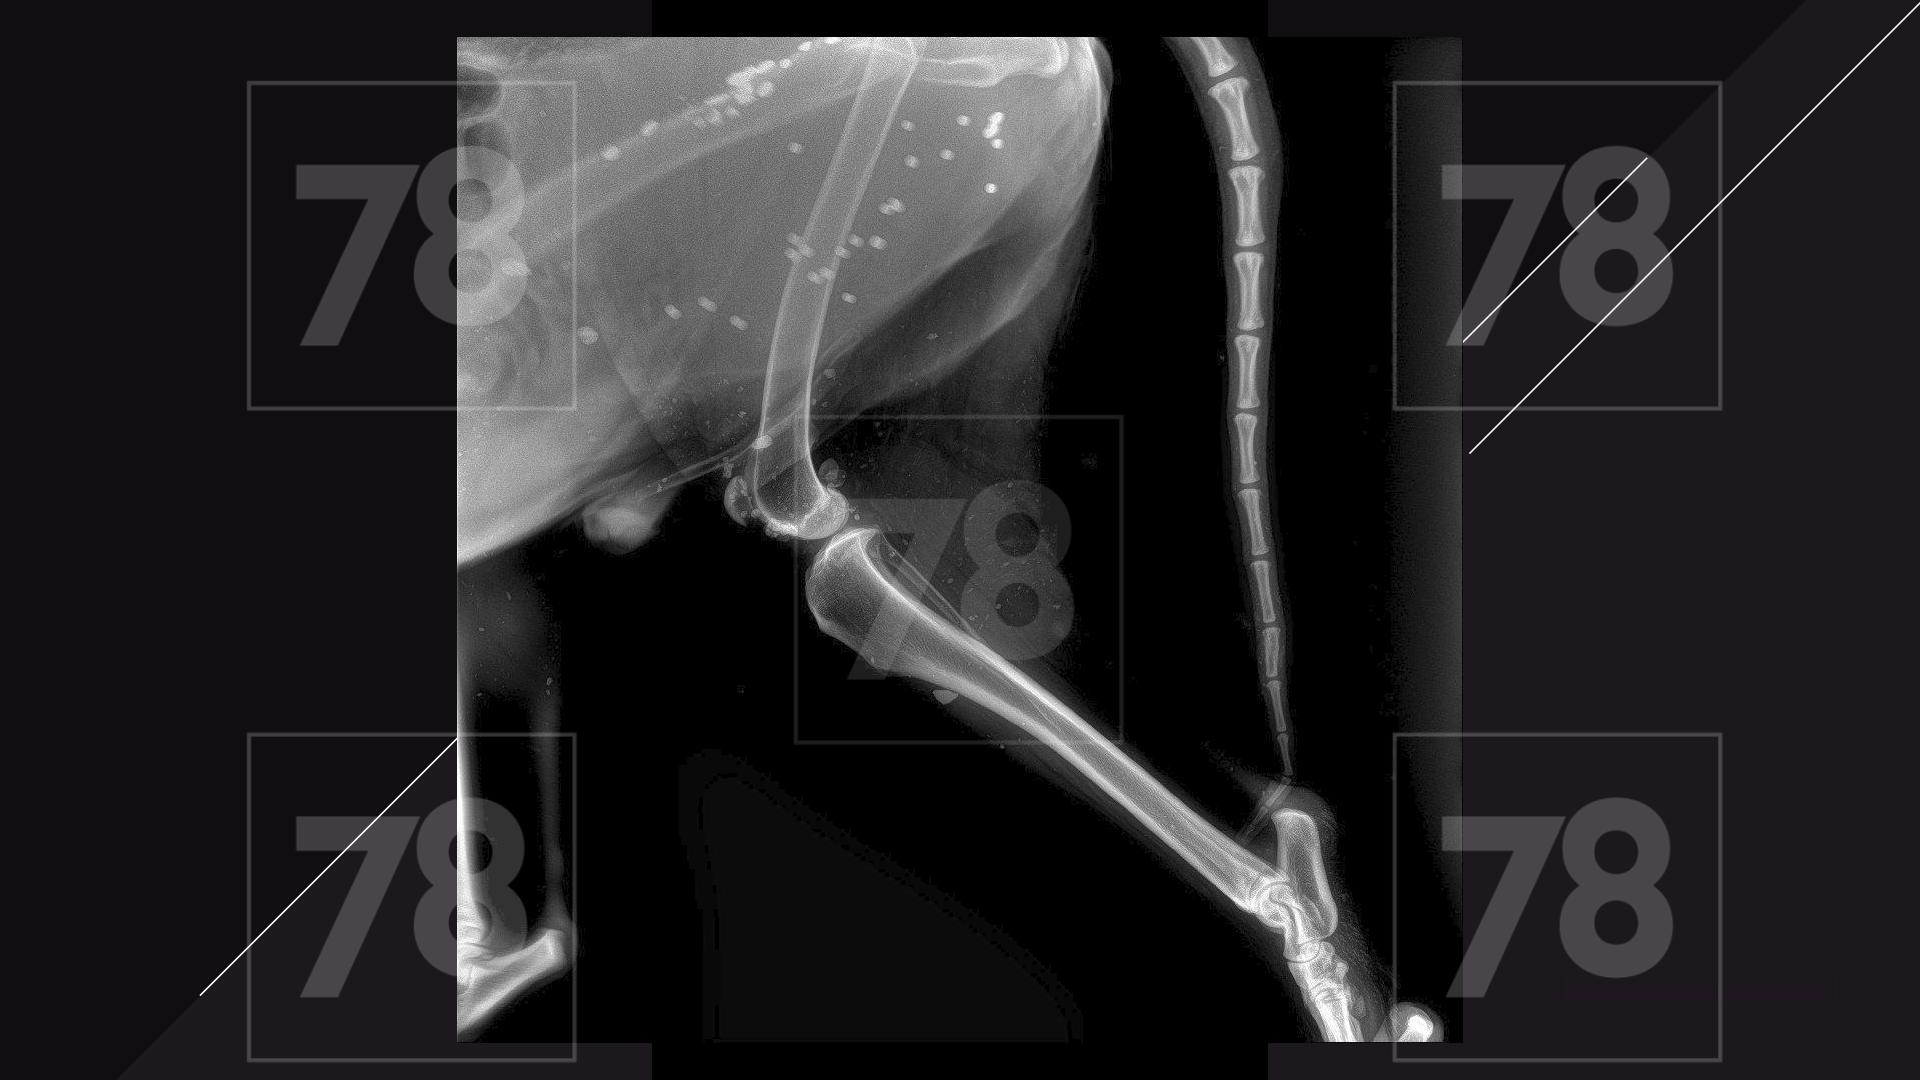

Врачи обнаружили у собаки множественные ранения пулями, как свежие, так и старые.